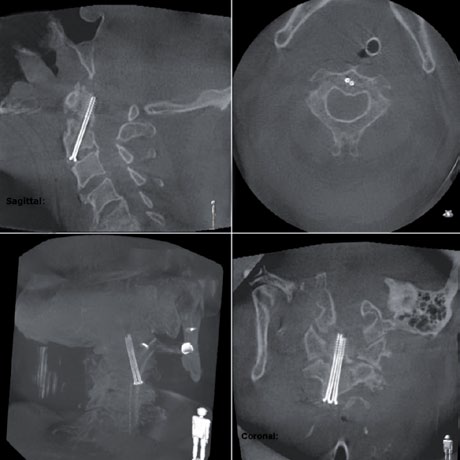

Gerade in empfindlichen Bereichen wie der zervikalen Wirbelsäule, oder auch bei komplexen orthopädischen und unfallchirurgischen Umstellungsosteotomien ist eine zuverlässige intraoperative Bildgebung essentiell für die sichere Platzierung der Implantate und die unmittelbare Ergebniskontrolle. Leistungsstarke mobile C-Bögen wie der Ziehm Vision RFD 3D ermöglichen eine intraoperative Kontrolle mit CT-ähnlicher Bildqualität innerhalb weniger Minuten.

Bei minimalinvasiven orthopädischen und traumatologischen Eingriffen bietet die mobile intraoperative Bildgebung zusätzliche Sicherheit für Patient und Chirurg. Durch die intraoperative 3D-Kontrolle können Fehllagen noch im OP-Saal erkannt und sofort korrigiert werden. So reduzieren sich postoperative CT-Kontrollen und Revisionen. Dadurch verringert sich das Risiko für den Patienten und gleichzeitig ergeben sich auch Kosteneinsparungen für das Gesundheitssystem.